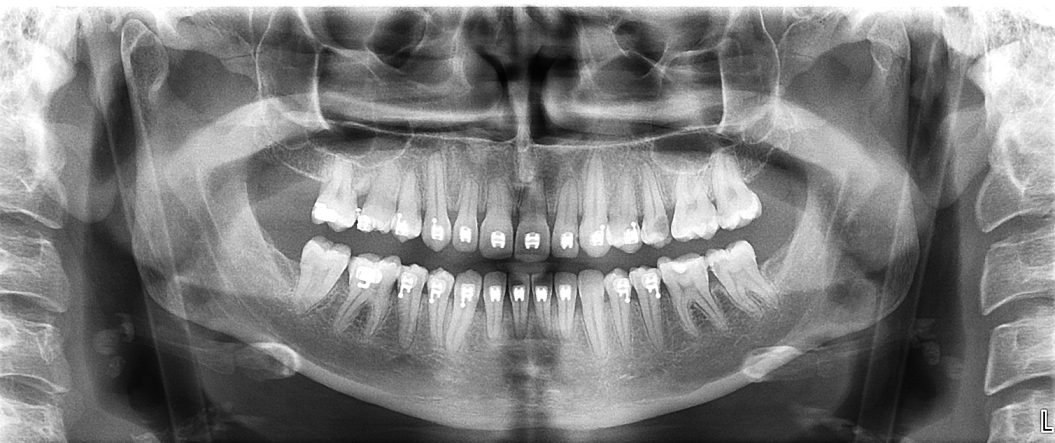

¿Por qué la radiografía convencional puede no ser suficiente?

Las radiografías bidimensionales, como la ortopantomografía o las periapicales, ofrecen una visión general, pero presentan limitaciones importantes en pacientes periodontales:

- Superposición de estructuras.

- Dificultad para valorar defectos óseos en profundidad.

- Imposibilidad de analizar correctamente la pérdida ósea vestibular y lingual.

- Distorsión de alturas óseas reales.

En situaciones complejas, estas limitaciones pueden llevar a infravalorar la severidad del daño óseo.